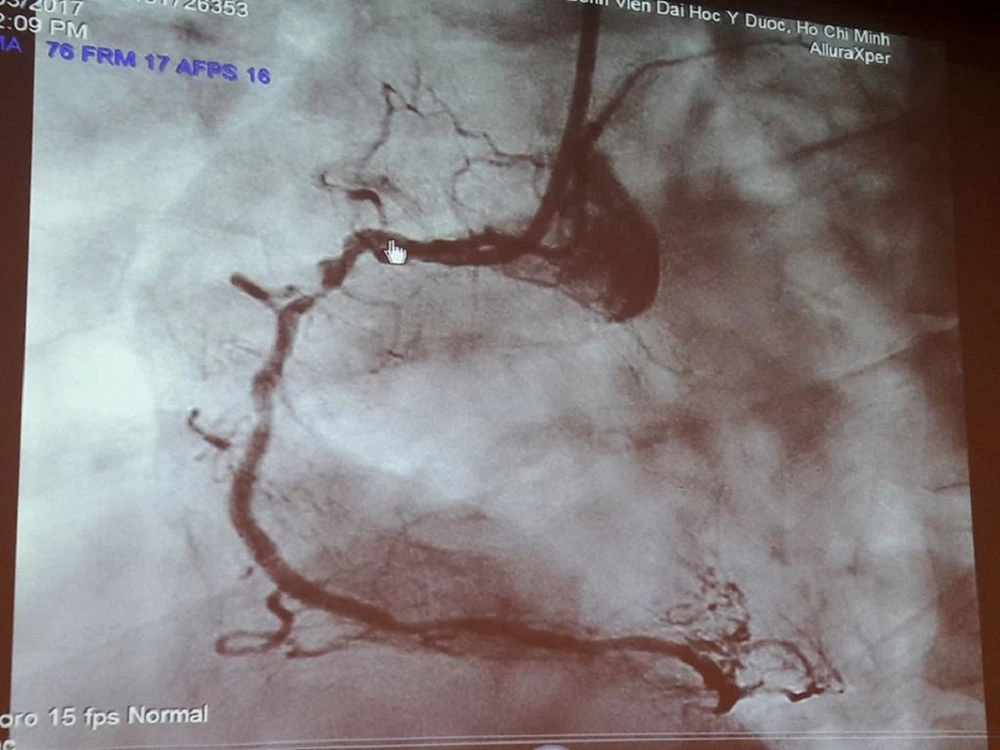

Nếu không được can thiệp cấp cứu để tải thông mạch máu bị tắc, khả năng tử vong của bệnh nhân sẽ rất cao Ảnh: HÀ PHƯỢNG

Tại đây, các y, bác sĩ BV An Bình đã nhanh chóng xử trí cấp cứu người bệnh bằng sốc điện, đặt nội khí quản để thở máy, dùng các thuốc điều trị rối loạn nhịp, các thuốc vận mạch để nâng huyết áp. Sau 15 phút hồi sức tích cực, tim người bệnh đập lại, huyết áp có nhưng rất thấp, đo điện tâm đồ lúc sau thấy có dấu hiệu nhồi máu cơ tim tối cấp thành dưới. Nếu không được can thiệp cấp cứu để tải thông mạch máu bị tắc thì gần như là khả năng tử vong rất cao.

Do đó, BV An Bình đã thông báo với bác sĩ can thiệp nội mạch của BV ĐH Y Dược qua điện thoại, quyết định chiến lược điều trị tiếp theo là chuyển khẩn người bệnh qua BV ĐH Y Dược để can thiệp mạch vành cấp cứu. 60 phút sau khi nhập viện, bệnh nhân đã thoát khỏi tình trạng nguy kịch.